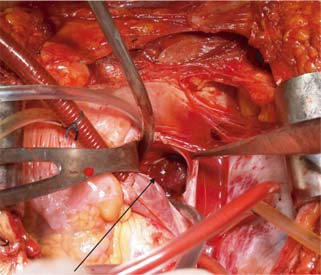

The surgical technique used for different levels of thrombus extension in our study is as follows. For level I (Figure 1) thrombus, vascular side clamps are used without occluding IVC inflow. The cavotomy defect is then sewn using a continuous prolene 4-0 suture. Level II thrombus (Figure 2A and B) often necessitates more extensive mobilization of the IVC. Proximal and distal control of IVC is necessary with ligation and division of lumbar veins to prevent significant blood loss. For the retrieval of thrombus, vascular clamps are used with clamping of the left renal vein in case of right-sided renal tumors and clamping of the right renal artery in case of left-sided renal tumors. The cavotomy defect is sewn using continuous prolene 4-0 suture. For level IV thrombi (Figure 3), a beating heart surgery with a simplified CPB technique was used for retrieval of thrombus from RA. For level IV thrombi, ligation of renal artery is followed by radical nephrectomy using chevron incision. The left renal vein is looped, and IVC below the renal vein is skeletonized for a length of about 5 cm to prepare it for IVC cannulation. A purse string is made on it using 4-0 prolene monofilament suture and the subhepatic portion of IVC is dissected. Then, median sternotomy is performed and pericardium is opened. Aortic purse-string suture with 3-0 prolene is taken on the ascending aorta. The intrapericardial portion of the superior vena cava (SVC) is looped, and a purse-string with 3-0 prolene is taken. Patient is heparinized with 300 Units/kg body weight of heparin. Aortic and venous cannulations are performed, and patient is put on complete CPB after both SVC and IVC are snugged with Rummel tourniquet. No vent cannula is put in. Patient is cooled to 35°C. On beating heart under normothermic CPB, RA thrombus (Figure 4) is extracted without cross-clamping the aorta. Right atriotomy is performed and tumor thrombus, which is organized and firm, is carefully retrieved. IVC is snugged at its junction with RA to prevent spillover from IVC into RA. Subhepatic IVC is incised longitudinally, and the tumor thrombus is extracted, using digital manipulation to ensure complete removal from retrohepatic IVC. Intermittent suctioning is performed using a pump sucker as hepatic veins are opened up. Cavotomy is closed using 4-0 prolene suture. After completely de-airing the RA, the atriotomy is also closed. Patient is gradually weaned off the bypass. “Patients were followed up quarterly in the first year, semiannually in the second year, and annually thereafter”.

Figure 1: Level 1 thrombus (HPE Squamous cell carcinoma) with arrows showing level 1 thrombus.